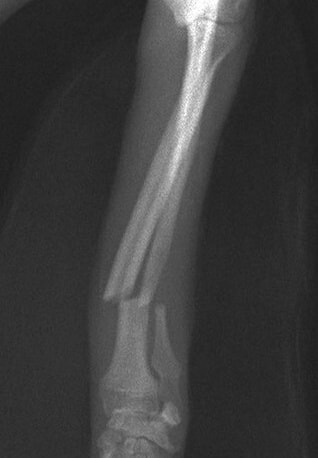

橈尺骨骨折 : 症例1 | 症例2 | 症例3 | 症例4 | 症例5 | 症例6 | 症例7

: 症例8 | 症例9 | 症例10 | 症例11 | 症例12 | 症例13 | 症例14

: 症例15 | 症例16 | 症例17 | 症例18 | 症例19 | 症例20 | 症例21

脛骨骨折 : 症例1 | 症例2 | 症例3 | 症例4 | 症例5